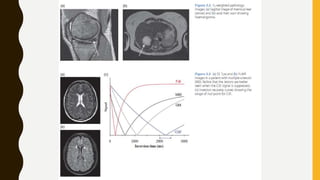

Dynamic Contrast Enhanced Magnetic Resonance Imaging

semiquantitative approach assesses enhancement over time (Tofts et al, 1991). There

are three distinct curves associated with prostate imaging (Fig. 2-31). Because of the

overlap of all three curve types with benign conditions, it is useful to combine these

approaches in a MP-MRI